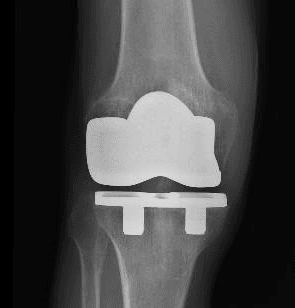

L’intervento di artroprotesi di ginocchio prevede la sostituzione chirurgica del femore distale e della tibia prossimale con protesi metalliche, associate a materiali plastici e/o ceramici. Quando necessario, si può includere anche la protesizzazione della rotula. Lo scopo principale di questa procedura è ripristinare un’articolazione stabile e funzionale, migliorando la capacità di movimento del paziente e alleviando il dolore, con conseguente miglioramento della qualità della vita.

Oggi sono disponibili diversi tipi di protesi, adattabili alle varie esigenze funzionali dei pazienti e ai diversi scenari osseo-legamentosi. Per le protesi totali si distinguono in generale impianti con conservazione (Cruciate Retaining – CR) o sacrificio (Posterior Stabilized – PS) del legamento crociato posteriore, con ulteriori sottogruppi di inserti a seconda delle necessità del paziente e della tecnica di impianto adottata. Per situazioni più complesse o per revisioni protesiche si possono utilizzare impianti semivincolati o a cerniera.